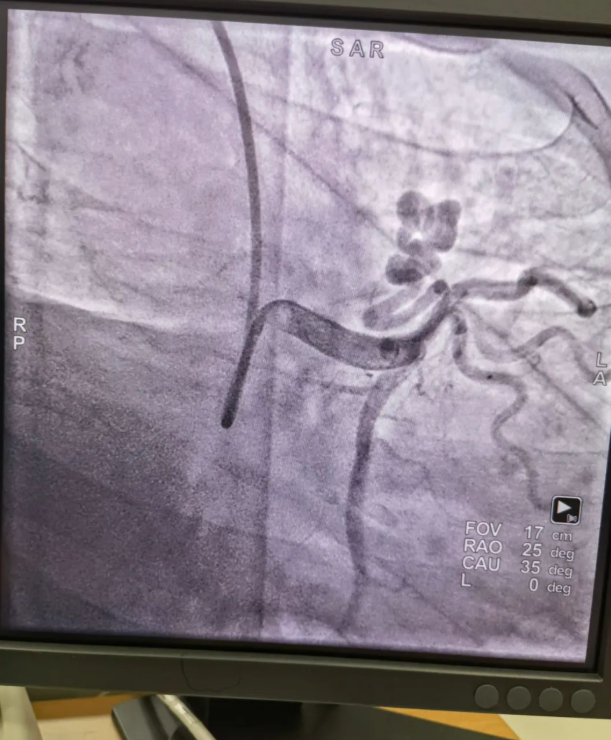

不久前,來自新疆的患者石先生去年至今反復(fù)胸悶、氣短、胸痛,就診于新疆某院,懷疑“冠心病”,住院行冠狀動(dòng)脈造影術(shù),石先生造影提示“冠狀動(dòng)脈肺動(dòng)脈瘺”,而他并非“冠心病”,所以給予的“冠心病”治療,效果不佳。出院后仍反復(fù)出現(xiàn)胸痛、胸悶、氣短等癥狀,經(jīng)親友介紹了解到西安國際醫(yī)學(xué)中心醫(yī)院心臟病醫(yī)院心臟內(nèi)科二病區(qū)曾廣偉主任,多年來潛心研究心臟病介入治療,成功主刀救治了許許多多高危復(fù)雜病例,尤其是在先心病及結(jié)構(gòu)性心臟病封堵,以及冠心病、心律失常射頻消融及起搏治療等方面積累了豐富的診療經(jīng)驗(yàn)。

此病例罕見,在曾廣偉從醫(yī)18年生涯里曾碰到有2個(gè)印象深刻的病例,患者分別是53歲和66歲,當(dāng)時(shí)建議患者入院進(jìn)行動(dòng)脈瘺的封堵術(shù),但患者和家屬考慮到這個(gè)手術(shù)案例極少,風(fēng)險(xiǎn)也高,均未接受手術(shù)治療建議,只是能采取藥物保守治療,出院后隨訪得知患者癥狀緩解效果不佳,后來在隨訪中也與53歲患者失去了聯(lián)系,而66歲患者因冠狀動(dòng)脈肺動(dòng)脈瘺出現(xiàn)反復(fù)心衰,在當(dāng)?shù)蒯t(yī)院藥物治療,短短2年時(shí)間,患者因?yàn)閯?dòng)脈瘺未及時(shí)手術(shù)失去了生命。所以此次患者石先生到訪,曾廣偉主任在詳細(xì)掌握病例資料基礎(chǔ)上,果斷建議進(jìn)行動(dòng)脈瘺的封堵術(shù)治療,為了提高手術(shù)成功率和精準(zhǔn)度,曾廣偉主任搜集相關(guān)診療資料,反復(fù)推演論證,經(jīng)過相當(dāng)充足的準(zhǔn)備工作,于5月18日成功進(jìn)行了封堵手術(shù),完全堵上了瘺口。

患者術(shù)后第2天,已經(jīng)沒有明顯的胸悶、氣短、胸痛等癥狀,目前身體狀態(tài)良好。本次手術(shù)曾廣偉主任及其團(tuán)隊(duì),采取從右手臂一根血管進(jìn)入,并在2小時(shí)之內(nèi)完美封堵,創(chuàng)口小,痛苦小。手術(shù)雖然難度大、風(fēng)險(xiǎn)高,相關(guān)案例也少,但是曾廣偉主任主刀即在巔峰,這樣一臺(tái)完美的手術(shù)靠的不是運(yùn)氣,是豐富的臨床手術(shù)經(jīng)驗(yàn),扎實(shí)的專業(yè)知識(shí)儲(chǔ)備,以及對醫(yī)療事業(yè)的孜孜追求。

冠狀動(dòng)脈瘺是指冠狀動(dòng)脈與心腔、冠狀靜脈、肺動(dòng)脈等的異常連接,是一種少見的先天性心臟病,發(fā)病率為1.3%。而冠狀動(dòng)脈肺動(dòng)脈瘺是冠狀動(dòng)脈與肺動(dòng)脈之間產(chǎn)生的一種血管性瘺口,導(dǎo)致冠狀動(dòng)脈里的血液流入肺動(dòng)脈里,使冠狀動(dòng)脈里血液流量減少,出現(xiàn)心肌供血不足,冠狀動(dòng)脈肺動(dòng)脈瘺會(huì)使患者出現(xiàn)胸部疼痛、胸悶、呼吸困難、頭暈、乏力等一系列癥狀,隨著疾病不斷進(jìn)展,可引發(fā)心功能的障礙和心肌缺血,肺動(dòng)脈會(huì)逐漸形成肺動(dòng)脈高壓,還可能導(dǎo)致動(dòng)脈瘤的破裂,甚至威脅病人的生命安全,所以早期發(fā)現(xiàn)和治療冠狀動(dòng)脈肺動(dòng)脈瘺,對病人的預(yù)后改善具有重要的意義。